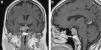

Reagudización de asma tras tratamiento quirúrgico de síndrome de Cushing

Asthma relapse after surgical treatment of Cushing's syndrome